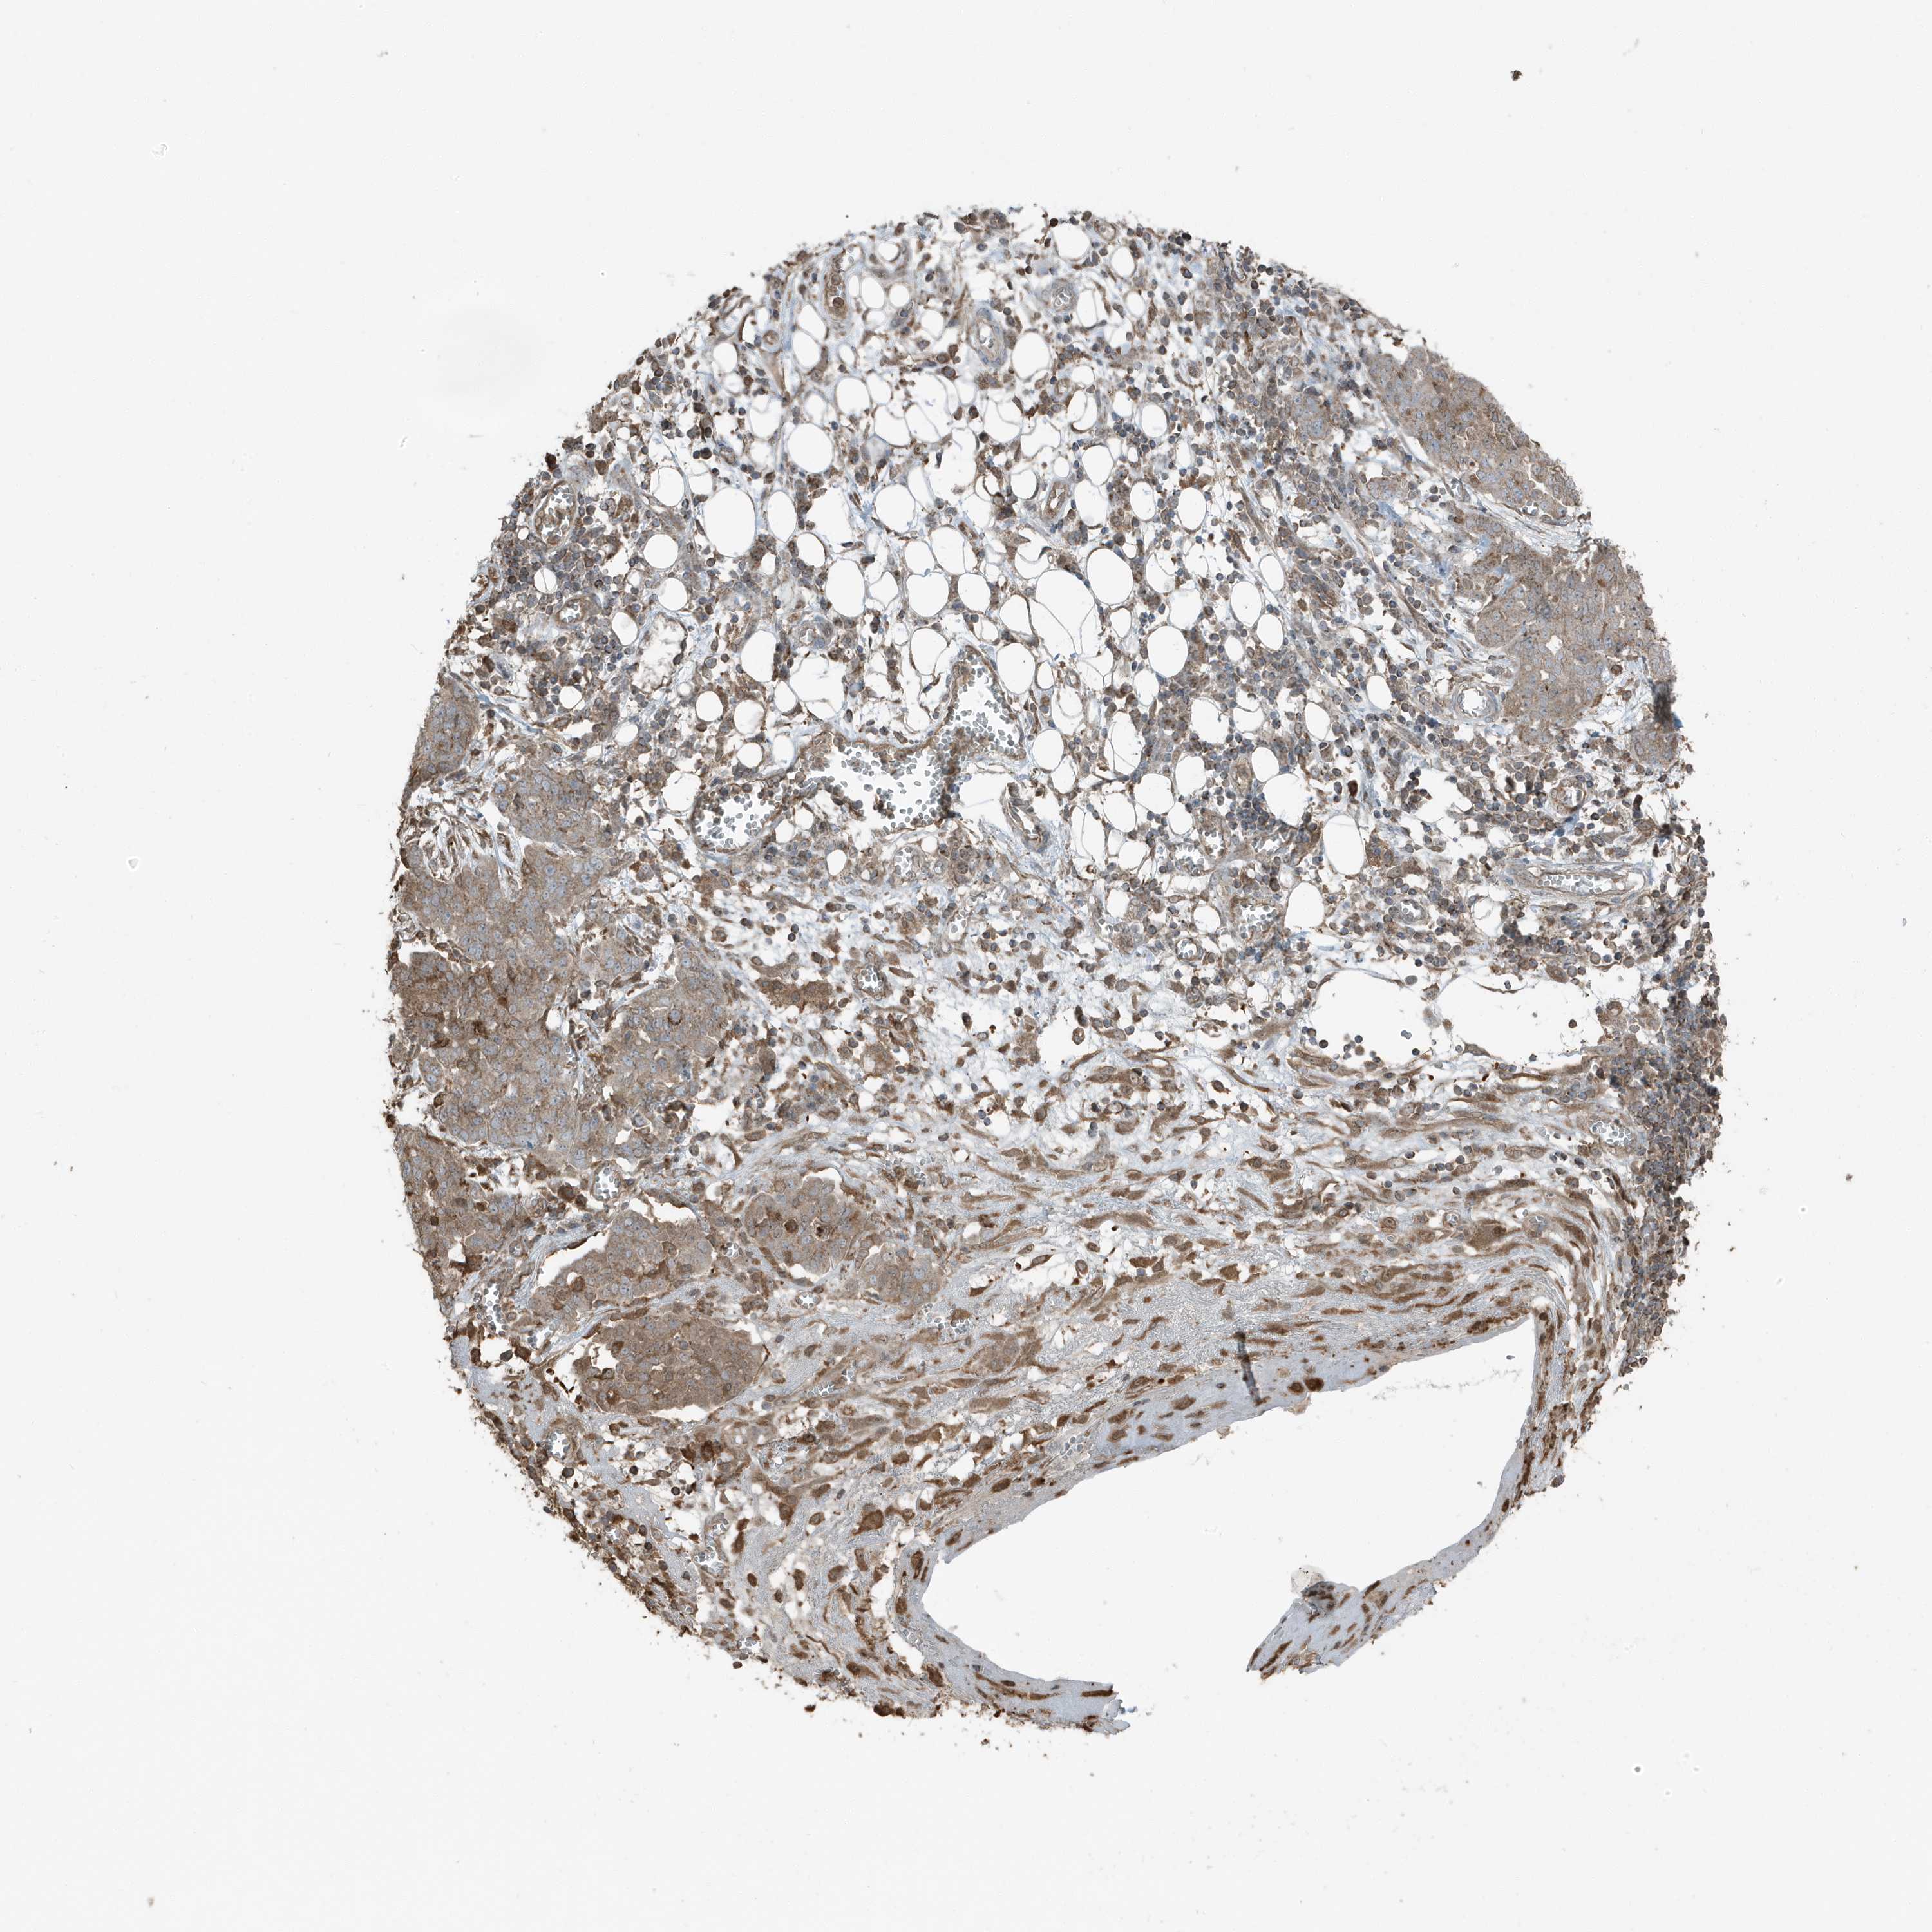

OVARIAN CANCER - Protein expressioni

A mouse-over function shows sample information and annotation data. Click on an image to view it in a full screen mode. Samples can be filtered based on level of antibody staining by selecting one or several of the following categories: high, medium, low and not detected. The assay and annotation is described here.

Note that samples used for immunohistochemistry by the Human Protein Atlas do not correspond to samples in the TCGA dataset.

Antibody stainingi

Antibody staining in the annotated cell types in the current human tissue is reported as not detected, low, medium, or high, based on conventional immunohistochemistry profiling in selected tissues. This score is based on the combination of the staining intensity and fraction of stained cells.

Each image is clickable and will lead to virtual microscopy that enables deeper exploration of all samples and also displays staining intensity scores, fraction scores and subcellular localization as well as patient and tissue information for each sample.

Antibody HPA035258

Staining

High

Medium

Low

Not detected

Intensity

Strong

Moderate

Weak

Negative

Quantity

>75%

75%-25%

<25%

None

Location

Nuclear

Cytoplasmic/membranous

Cytoplasmic/membranous,nuclear

Cystadenocarcinoma, serous, NOS

Carcinoma, endometroid

Cystadenocarcinoma, mucinous, NOS

Carcinoma, NOS